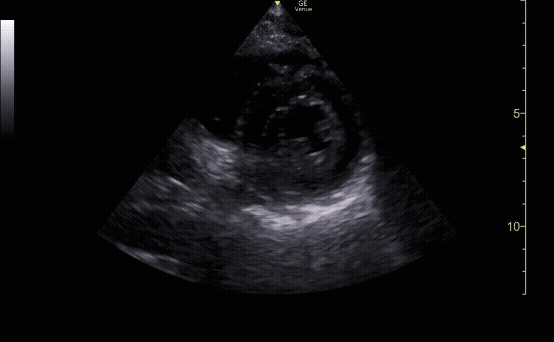

Parasternal short view showing the left ventricle and right ventricle at the level of the papillary muscles.

c/o Kyle Ackerman, MD